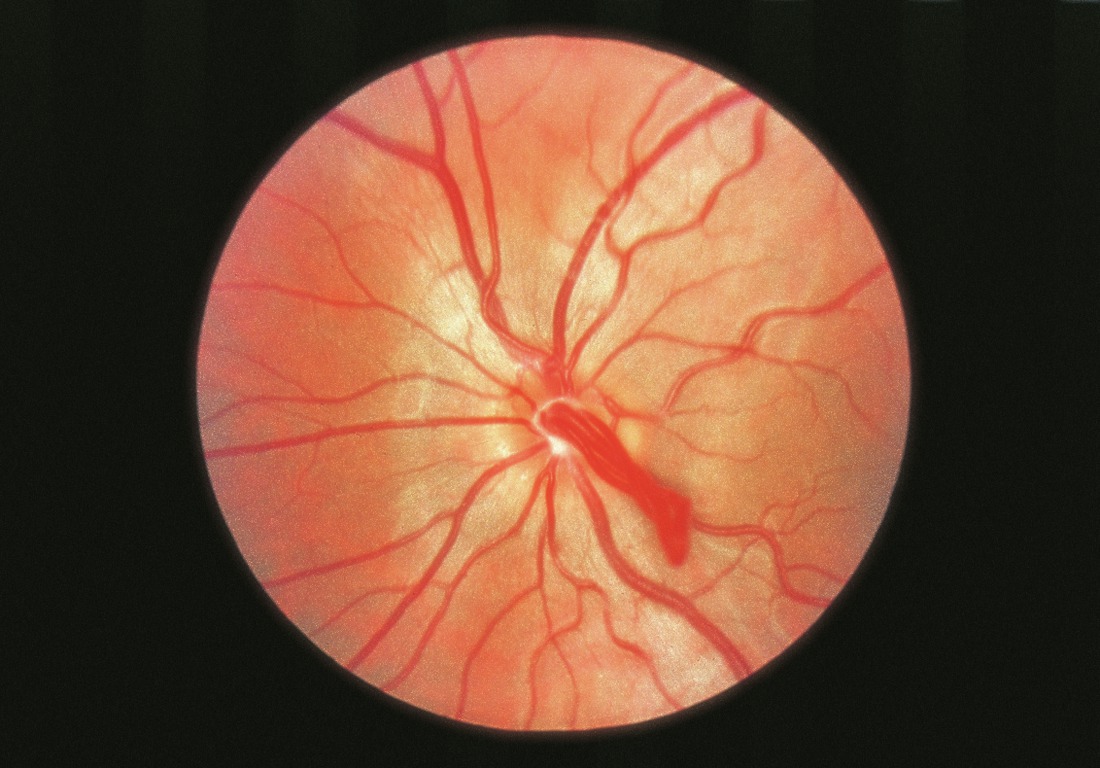

Boucles vasculaires prépapillaires

Initialement considérées comme des restes de l'artère hyaloïde, les boucles vasculaires prépapillaires sont des vaisseaux normaux naissant de la papille qui se développent au sein de la papille de Bergmeister avant de retourner à la rétine (fig. 16-6). Les boucles s'étendent généralement sur moins de 5 mm dans le vitré. Ces vaisseaux peuvent suppléer un ou plusieurs quadrants rétiniens. L'angiographie à la fluorescéine (AF) a montré que 95 % de ces vaisseaux sont artériels et 5 % sont veineux. Les complications comprennent l'occlusion de branche artérielle de la rétine, l'amaurose fugace et l'hémorragie intravitréenne.

Figure 16-6

Photographie du fond d'œil d'une boucle vasculaire prépapillaire.

(Remerciements au Dr Gilbert Grand.)